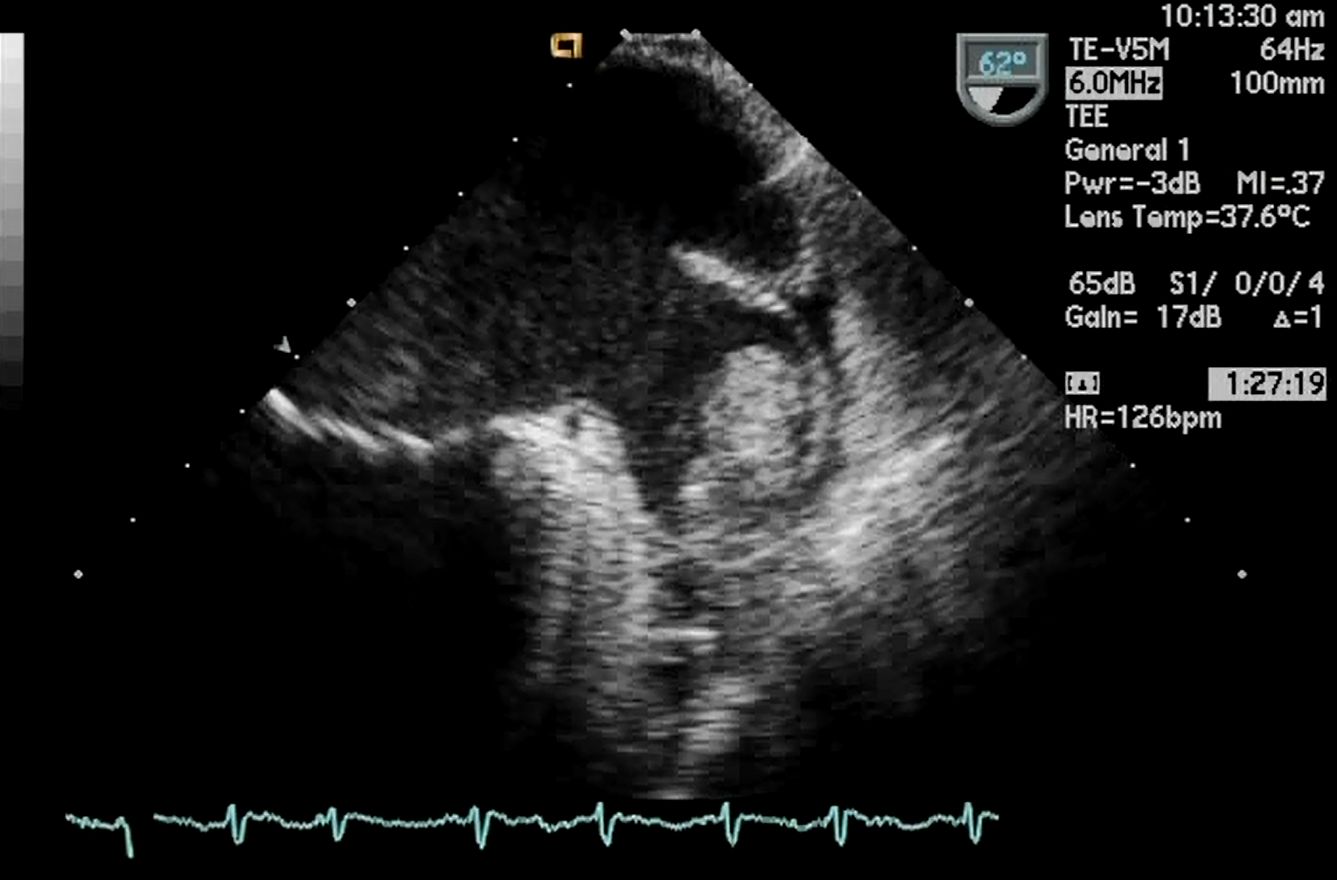

経食道心エコーは、超音波探触子を食道内に挿入して心臓を観察する検査で、体表面では評価困難な弁の性状や左房内の血栓などをより鮮明に評価が可能です。当科では、毎週2回(水、木)施行しております。当院エコー室で使用している、経食道エコーの探触子は3Dエコーの表示が可能で、より詳細に弁や欠損孔等の観察が可能です。

また、心臓血管外科の僧帽弁形成術などの評価なども経食道心エコーを用いて手術室にて行っております。ハイブリット手術室では、経皮的心房中隔欠損閉鎖術、経皮的卵円孔閉鎖術、経皮的大動脈置換術(TAVI)、経皮的僧帽弁接合不全修復術(M-TEER)、経皮的左心耳閉鎖術など心臓の構造的疾患に対してカテーテルによる治療が盛んにおこなわれており、治療のガイドを担うため経食道心エコーが行われています。